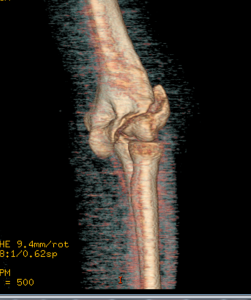

BGO's latest Champion patient comes from London, KY - Ms. Sydney Parker. Sydney is an animal lover, and was injured after a fall from her horse in October of 2018. She fractured and dislocated her elbow, which unfortunately led to surgery in October of 2018 - a complicated procedure that required an open reduction internal fixation as well as an ulnar nerve decompression and transposition. Sydney had fractured her trochlea, lateral condyle of her elbow, as well as her olecranon.

Dr. Donegan, BGO's shoulder and elbow specialist, said this about Sydney and her injury: "Sydney's fracture was very severe and involved the joint surface of the elbow. As a result, we needed to align the pieces anatomically to decrease her risk of arthritis in the long term and increase her range of motion and function. From the instant I met with Sydney and her family, you could tell she was going to keep a positive attitude and work to get better. She has an optimism about her that inspires others around her!"